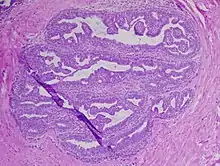

| Intraductal papilloma of breast, H&E, 10x | |

A papilloma (plural papillomas or papillomata) (papillo- + -oma) is a benign epithelial tumor[1] growing exophytically (outwardly projecting) in nipple-like and often finger-like fronds. In this context, papilla refers to the projection created by the tumor, not a tumor on an already existing papilla (such as the nipple).